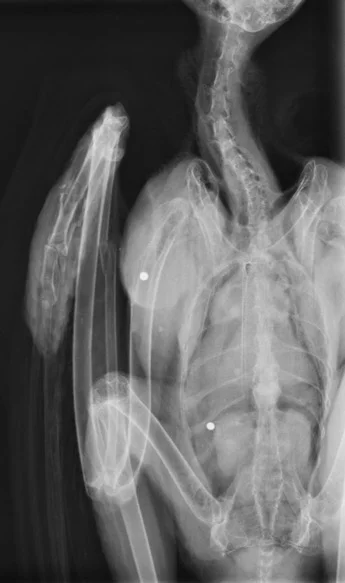

The two white dots of this x-ray of the injuredbuzzard indicate where it had been shot.

X-rays were taken and it was then that the shocking truth was discovered - the bird hadn’t been mauled at all, it had been shot and the nature of the injuries also indicated that it had been shot while on the wing.  The poor bird had not only sustained a badly broken wing, but the x-rays showed clearly that it had been shot in both a leg and the stomach.  Apart from the obvious implications of being shot, the buzzard could easily have died from shock or from poisonous lead getting into its system - fortunately, it appeared that tissue had grown around the lead shot and had sealed it from the rest of the bird’s system, thus saving it from lead poisoning.